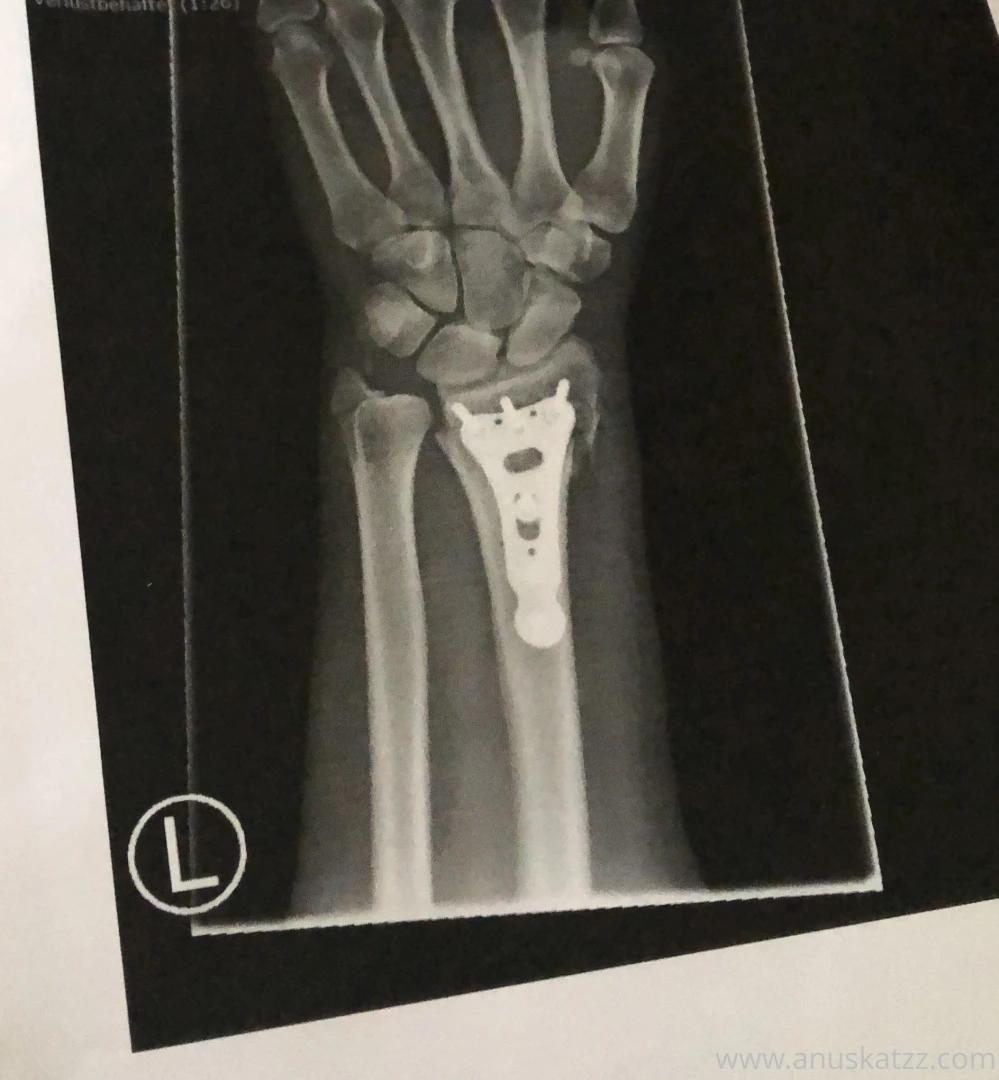

I got a titan plate stuck to my bones who help me heal the broken arm I got them implemented trough operation who is now 3 days ago The pain is unbelievable I feel the unnatural connection between bone and plate it directly send the pain to my big scare on the side of my arm I hope I will heal fast and my body will be strong enough for this intense intervention Next week I have again an appointment in the hospital to see if everthing work properly